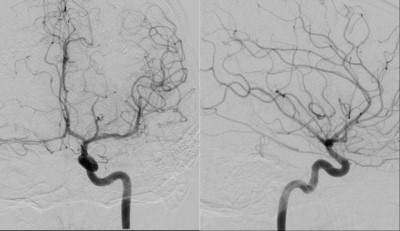

This is a 24 year old female who presented to the ER 2 years prior with first time seizure.

- Pre-Op